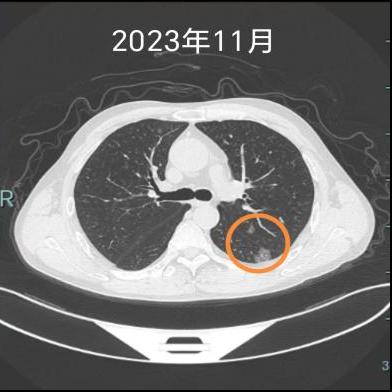

老杨是个地道的“老烟枪”,三十多年的烟龄,手指头都被熏得焦黄。直到两年前他才把烟戒了,因为那时单位体检,在他左下肺发现了一个磨玻璃结节。老杨心里一慌:“大夫,这不会是癌吧?”

“除了戒烟,还要记得定期复查,有什么不舒服的也能及早治疗。”医生提醒老杨。而接下来的两年复查中,老杨的左上肺出现了明显的实性结节,并有胸膜牵拉表现,提示恶性可能。他再次选择来到医院心胸外科就诊。

“有些早期肺癌,就像埋在土里的种子,第一颗被我们挖掉了,但土壤里可能还藏着另一颗,或者因为长期吸烟造成的‘坏环境’,让新的种子在别处发芽了。”心胸外科专家团队为老杨详细解释了他的病况,安抚了他焦虑的心情,很快便开展了胸腔镜下左上肺亚肺叶切除术,标本可见明显的胸膜凹陷,剖开可见两枚结节。最终病理明确诊断:是腺癌!